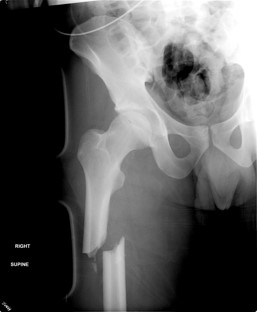

I found a quote recently by English novelist and poet, George Meredith, that says, “There is nothing the body suffers the soul may not profit by.” With all my body has endured – the broken neck, two fractured thoracic vertebrae, one snapped femur, a burst appendix, four different stage IV pressure sores, close to a dozen kidney stone surgeries, countless urinary tract infections, and a near-death experience from sepsis – it was probably inevitable that I started seeing things through a far more spiritual lens.